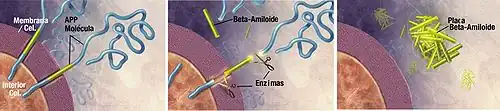

Las placas neuríticas están constituidas por pequeños péptidos de 39-43 aminoácidos de longitud, llamados beta-amiloides (abreviados A-beta o Aβ). El beta-amiloide es un fragmento que proviene de una proteína de mayor tamaño conocida como Proteína Precursora de Amiloide (APP, por sus siglas en inglés). Esta proteína es indispensable para el crecimiento de las neuronas, para su supervivencia y su reparación postdaño.[85][86]

En la enfermedad de Alzheimer, un proceso aún desconocido es el responsable de que la APP sea dividida en varios fragmentos de menor tamaño por enzimas que catalizan un proceso de proteólisis.[87]

Uno de estos fragmentos es la fibra del beta-amiloide, el cual se agrupa y deposita fuera de las neuronas en formaciones microscópicamente densas conocidas como placas seniles.[19][88]

Su componente principal es el péptido beta-amiloide de 42 aminoácidos (βA42), en cuyo proceso de producción es fundamental la participación de la γ-secretasa, la cual depende a su vez de las presenilinas (PSEN).[61]

Hay dos tipos, PSEN 1 y PSEN 2, con una estructura similar. La función principal que desempeñan ambas PSEN consiste en el procesamiento proteolítico de numerosas proteínas de membrana de tipo 1, entre ellas la APP, formando parte de la γ secretasa; de ahí la importancia de las PSEN en la enfermedad de Alzheimer, ya que a través de la regulación de la γ secretasa determinan la forma de Aβ que se genera y por tanto su acumulación en el tejido cerebral.[61][64][65]